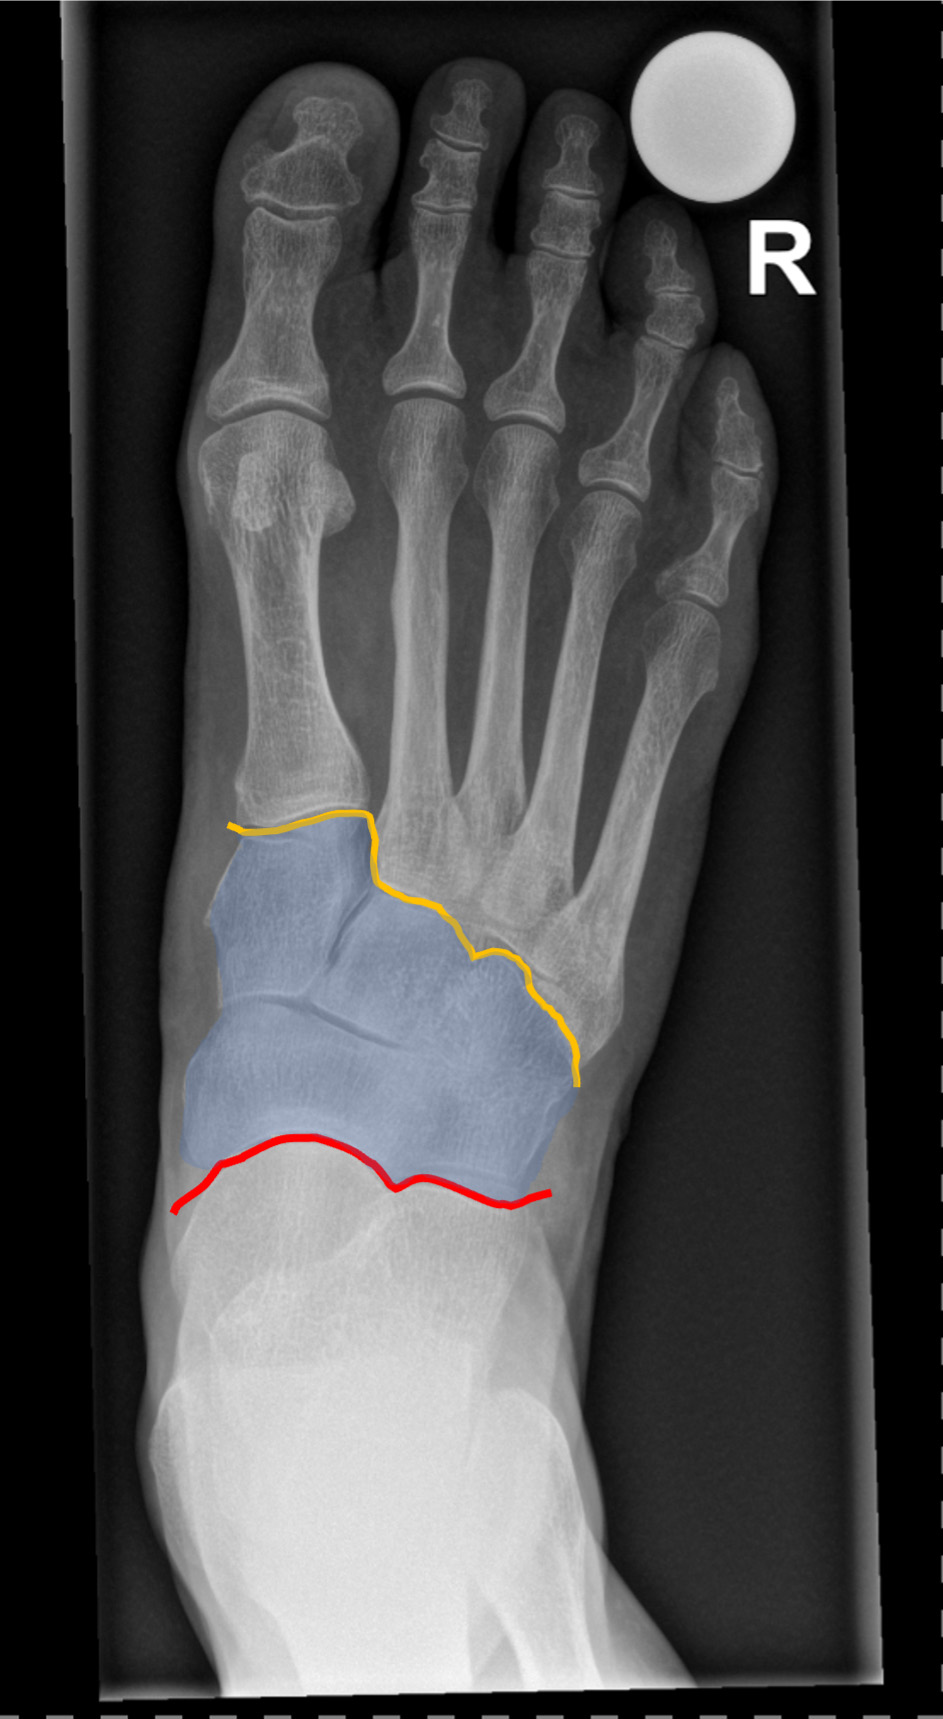

Röntgenbilder sind zur Diagnosestellung hilfreich. Zum einen zeigen sie meist bereits die Arthrose der Gelenke, zum anderen kann ihre Stabilität beurteilt werden. Aufgrund der Form des Fussgewölbes sind Röntgenbilder mehrerer Ebenen notwendig, um eine zuverlässige Aussage treffen zu können. Unter Umständen ist zusätzlich eine Magnetresonanztomographie (MRT bzw. engl. MRI für magnetic resonance imaging) nötig, um das genaue Ausmass der Arthrose und Verletzung des Mittelfusses bestimmen zu können.

Führt die konservative Therapie nicht zum Erfolg, kommt eine Operation in Frage. Bei störenden Osteophyten und nur geringfügiger Arthrose kann ein Abtragen des Knochens zum Erfolg führen. Ist die Arthrose fortgeschritten, fällt die Wahl meistens auf eine Versteifung (Arthrodese). Die betroffenen Gelenke werden dazu durch Schrauben oder Platten fixiert. Da die Mittelfussgelenke wenig zur Gesamtbewegung des Fusses beitragen, ist der Einfluss der Versteifung auf den Bewegungsumfang des Fusses gering. Dadurch ist gehen auch nach der Versteifung weiterhin gut möglich.